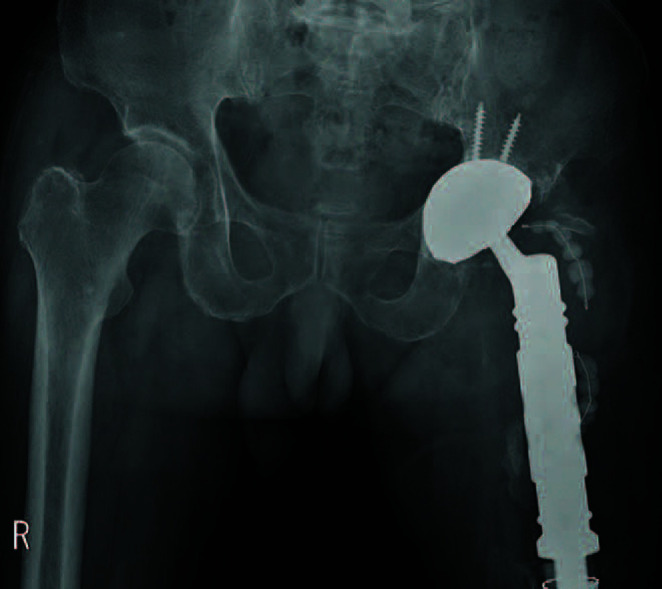

全髋关节置换术后脱位发生率约为 1%,但翻修手术后的发生率要高得多。为防止脱位,建议使用较大的股骨头,并引入了双活动股骨头。然而,在关节周围软组织挛缩的病例中,将双活动股骨头缩小至髋臼组件是很困难的。一位72岁的男性患者因假体周围关节感染而接受了两阶段的MUTARS®翻修手术。翻修手术两个月后,髋关节脱位,尝试了人工复位,但脱位再次发生。在另一次使用双活动轴承进行翻修时,髋关节周围的软组织太紧,无法缩小。为了解决这个问题,首先将双活动度轴承头重新定位到髋臼窝中,然后组装植入物的骺端部分。

Dislocation after a total hip arthroplasty occurs in approximately 1% of patients; however, the frequency is much higher after revision surgery. To prevent dislocation, use of a larger femoral head is recommended, and a dual mobility femoral head has been introduced. However, reducing the dual mobility femoral head to the acetabular component is difficult in cases involving contracture in the soft tissue around the joint. A 72-year-old male patient who developed a periprosthetic joint infection underwent two-stage revision surgery using MUTARS®. Two months after the revision, the hip joint became dislocated and manual reduction was attempted; however, dislocation occurred again. During another revision using a dual mobility bearing, the soft tissue around the hip joint was too tight to reduce. The problem was overcome by first repositioning the dual mobility head into the acetabular socket, followed by assembly of the diaphyseal portion of the implant.